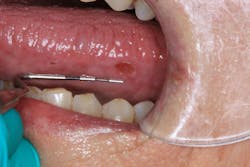

Clinical assessment revealed overall red, inflamed tissue throughout the oral cavity. Most notably present were large, ulcerlike lesions on the right and left lateral borders of the tongue (figures 1 and 2). The edges were well-defined and the red center slightly concave and very tender to palpation. Further, the vestibular tissue, upon the slightest touch, sloughed and hemorrhaged easily. Angular cheilitis was observed, and opening was painful (figure 3).